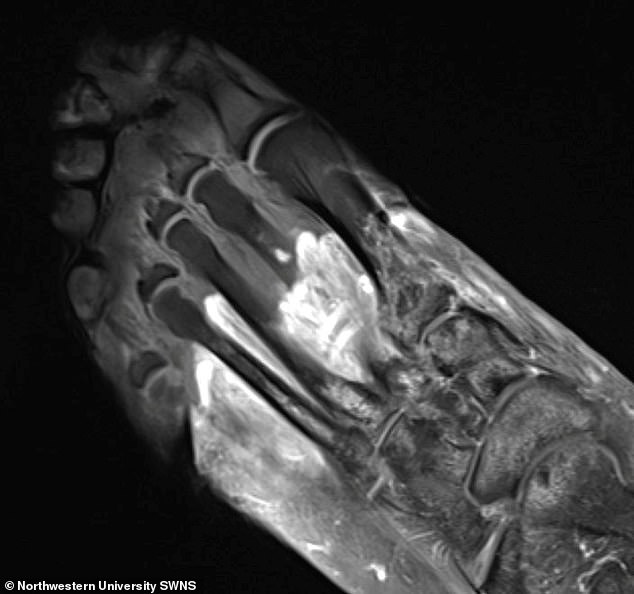

Ảnh chụp của một bệnh nhân COVID-19 cho thấy một phần bàn chân bị hoại thư.

Trong nghiên cứu của Đại học Northwestern, các nhà khoa học sử dụng các kỹ thuật hình ảnh khác nhau bao gồm chụp CT, MRI và siêu âm, để hình dung nguyên nhân gây hoại thư và các cơn đau cơ và khớp lâu dài ở bệnh nhân COVID-19.

Ảnh chụp y khoa của các bệnh nhân gặp phải các triệu chứng này cho thấy COVID-19 có thể khiến hệ miễn dịch của cơ thể tự tấn công chính nó, dẫn đến các vấn đề thấp khớp kéo dài.

Các nghiên cứu trước đây cũng tìm ra mối liên hệ giữa nhiễm virus corona và đau cơ hoặc khớp, nhưng đây là lần đầu tiên các triệu chứng này được minh họa qua hình ảnh y khoa.